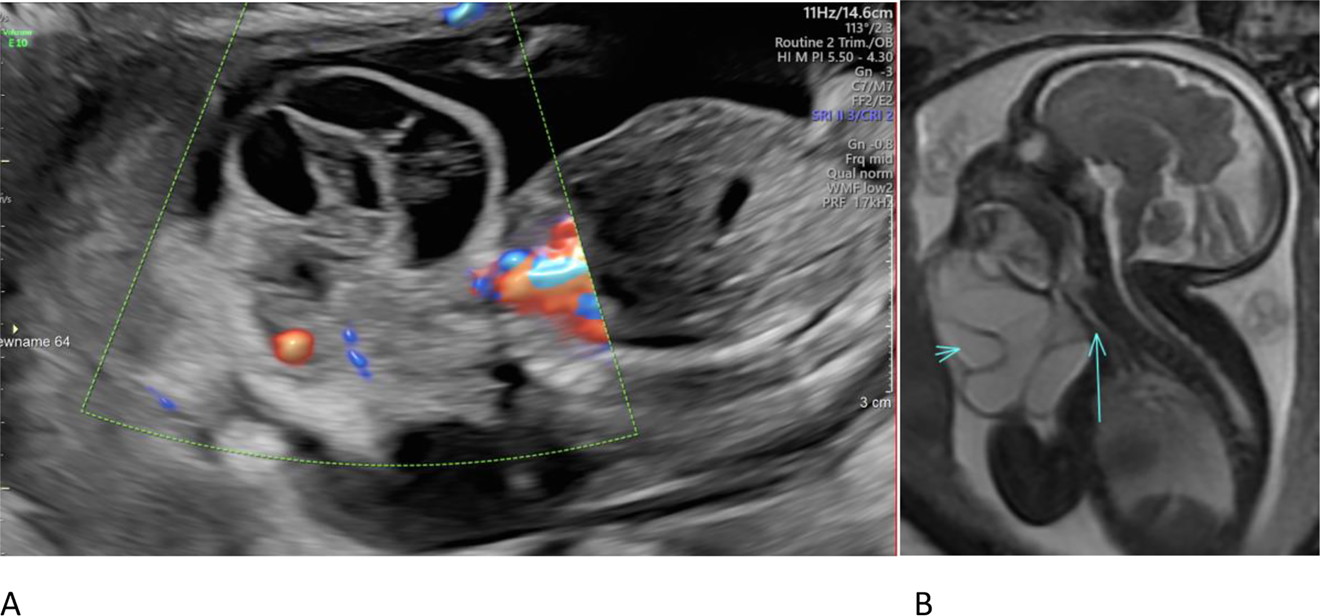

A pregnant 28-year-old G4P2 female was referred to maternal fetal medicine at 21 weeks gestation with concern for a fetal neck mass. The mother reported a history of preeclampsia resulting in preterm delivery with a past pregnancy but was otherwise healthy. Fetal ultrasound performed at 21 weeks revealed a complex cystic mass with internal septations originating off of the right side of the fetal neck. There was no definite internal doppler flow. In addition to follow up ultrasounds, the patient also underwent fetal MRI at 32 weeks. The MRI confirmed the presence of a complex cystic neck mass, which increased in size. The mass extended in close proximity to the fetal airway; however, at the time of the MRI, the airway was visualized and patent. There were no internal calcifications in the mass, and the fetal thyroid appeared normal. A diagnosis of lymphatic malformation was made on the basis of the prenatal imaging (Figure 1). Follow up ultrasounds throughout gestation showed continued growth of the neck lesion.

Figure Images at different weeks of pregnancy.

(A) Fetal ultrasound sagittal image at 21 weeks demonstrated a septated cystic neck mass with absent internal blood flow. (B) Fetal MRI T2 FIESTA sagittal image at 32 weeks demonstrates a cystic neck mass (short arrow) with oral cavity involvement and abutment of the trachea (long arrow).